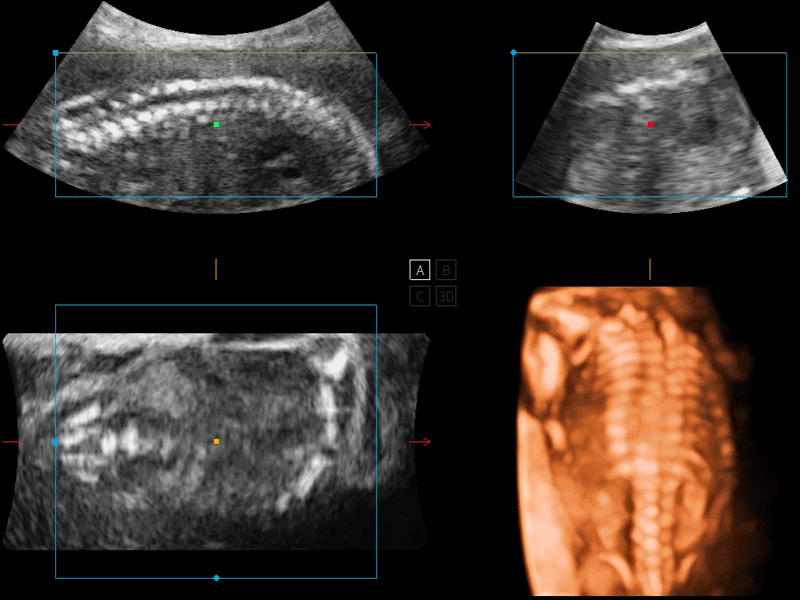

開立醫(yī)療通過不斷的技術(shù)創(chuàng)新,為大眾的生命健康提供持續(xù)關(guān)愛。P12 Plus采用全新一代超聲成像平臺,新平臺旨在將真實還原組織解剖結(jié)構(gòu)作為首要目標(biāo)。平臺采用全新集成化硬件模塊,搭載新一代芯片,系統(tǒng)性能得到大幅提升,為您的診斷提供了豐富的臨床信息。優(yōu)異的圖像表現(xiàn),豐富的探頭配置,全面的應(yīng)用功能,為您日常診斷提供了可靠的助手。

P12 Plus

彩色多普勒超聲診斷系統(tǒng)